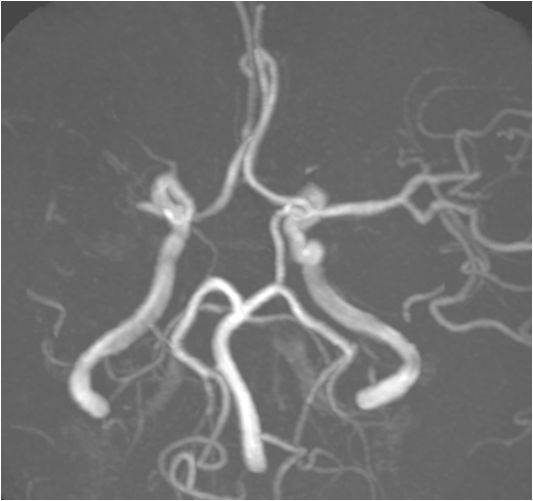

入院急查血未见明显异常指标,急查头部MRI+MRA:右侧半卵圆中心、右侧侧脑室旁多发急性脑梗死,右侧大脑中动脉重度狭窄,分枝稀疏。

分析该患者:影像学提示右侧大脑中动脉闭塞,不断进展的发病过程,提示发病机制为低灌注,确切地说是在动脉粥样硬化慢性狭窄基础上的急性闭塞,TOAST分型考虑大动脉闭塞型。药物治疗已经没有太积极的办法,患者有不断加重趋势,家属很焦急,血管内治疗能否作为最后一根救命稻草,力挽狂澜?